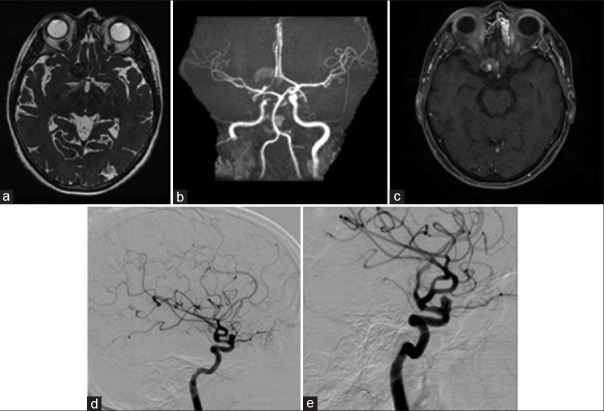

血流分流支架越来越多地用于颅内动脉瘤的治疗,特别是当存在不利于线圈栓塞的因素时,如颈部宽和动脉瘤尺寸大。然而,它的使用并不能保证成功,特别是在巨大病变中,未能获得动脉瘤闭塞会导致动脉瘤壁长期不稳定,导致动脉瘤生长和晚期破裂。我们提出的情况下,65岁的妇女谁遭受晚期动脉瘤扩张和破裂,2年零4个月后,分流治疗巨大的眼段动脉瘤。虽然尚未完全了解,但这种现象的病理生理学有一个必要因素:不完全的动脉瘤闭塞。当出现这种情况时,主要有两个因素:支架置入后囊内血流的增加以及部分血栓形成和支架本身的存在引起的局部炎症。为了防止这种并发症,必须确保动脉瘤完全闭塞,并鼓励使用联合技术。

Flow-diverting stents have been increasingly utilized for the treatment of intracranial aneurysms, especially when there are factors that go against coil embolization, such as wide neck and large aneurysm size. However, its use does not guarantee success, especially in giant lesions, and failure to obtain aneurysmal obliteration can result in long-term instability of the aneurysmal wall, leading to aneurysmal growth and late rupture. We present the case of a 65-year-old woman who suffered from a late aneurysmal dilation and rupture, 2 years and 4 months after flow-diverting treatment of a giant ophthalmic segment aneurysm. Although not fully understood, the pathophysiology of this phenomenon has one necessary factor: incomplete aneurysmal obliteration. When this scenario is present, two main factors take place: the augmentation of intrasaccular blood flow after stent delivery and the local inflammation caused by partial thrombus formation and the presence of the stent itself. To prevent this complication, complete aneurysmal obliteration must be assured, and the use of combined techniques is encouraged.